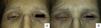

We present the case of a 55-year-old woman diagnosed with lobular breast carcinoma 15 years earlier. The patient was referred to our unit for a 1-year history of lesions that had arisen in the cervical region and that had extended to the upper third of the back and chest. Physical examination revealed hard, well-defined, edematous, erythematous papules and plaques in the posterior cervical region (Fig. 1), and localized erythema of all 4 eyelids that infiltrated to the deeper planes and interfered with eye opening (Fig. 2A) and closure (Fig. 2B).